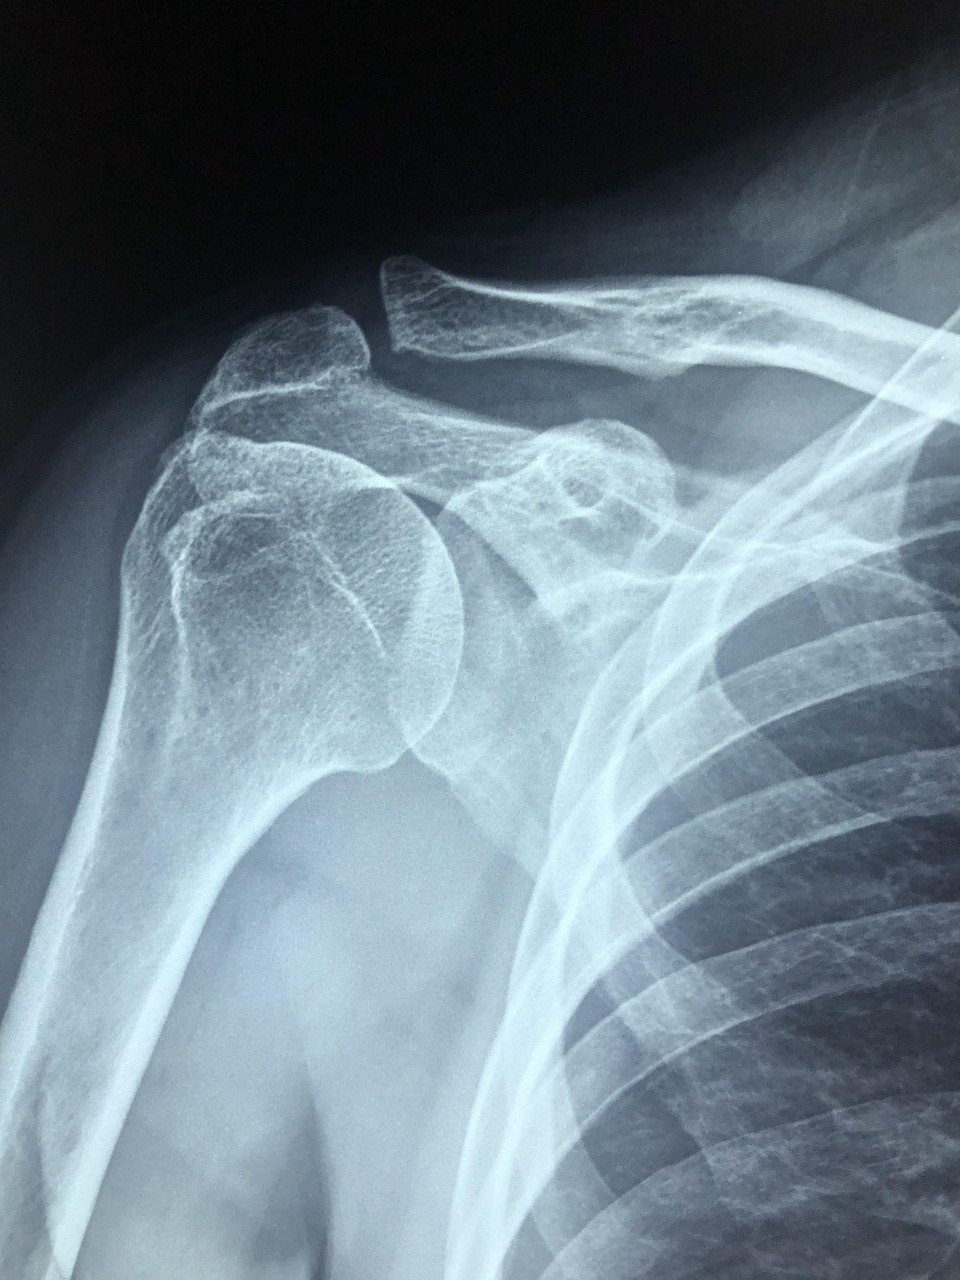

많은 분들이 병원을 찾으면 물어보는 질문 중 하나입니다. 특히 오십견, 회전근개 손상, 석회화건염 등으로 인해 어깨 통증이 극심할 때, 스테로이드 주사가 빠른 통증 완화를 돕는다고 알려져 있습니다.

스테로이드 주사는 흔히 ‘염증 주사’라고 불리며, 염증 반응을 줄여 통증을 빠르게 완화하는 데 큰 역할을 합니다. 특히 어깨 통증의 원인 중 상당수는 염증 반응과 관련이 있습니다. 오십견(유착성 관절낭염), 회전근개 손상, 석회화건염 등은 모두 어깨 관절 내 조직에 염증이 발생하면서 통증과 운동 제한을 유발합니다. 이때 스테로이드 성분이 염증 매개 물질을 억제해 부종 감소와 통증 완화를 이끌어내는 것입니다.

어깨 스테로이드 주사 효과는 단순히 맞는 것에 있지 않고, 언제 맞느냐가 핵심입니다. 예를 들어, 어깨 통증이 시작되자마자 무조건 주사를 맞는 것은 권장되지 않습니다. 초기 단계에는 약물치료와 물리치료만으로도 충분히 호전될 수 있기 때문입니다. 반대로 이미 석회화가 심하게 진행되었거나 회전근개가 완전히 파열된 경우에는 주사만으로는 큰 효과를 기대하기 어렵습니다.